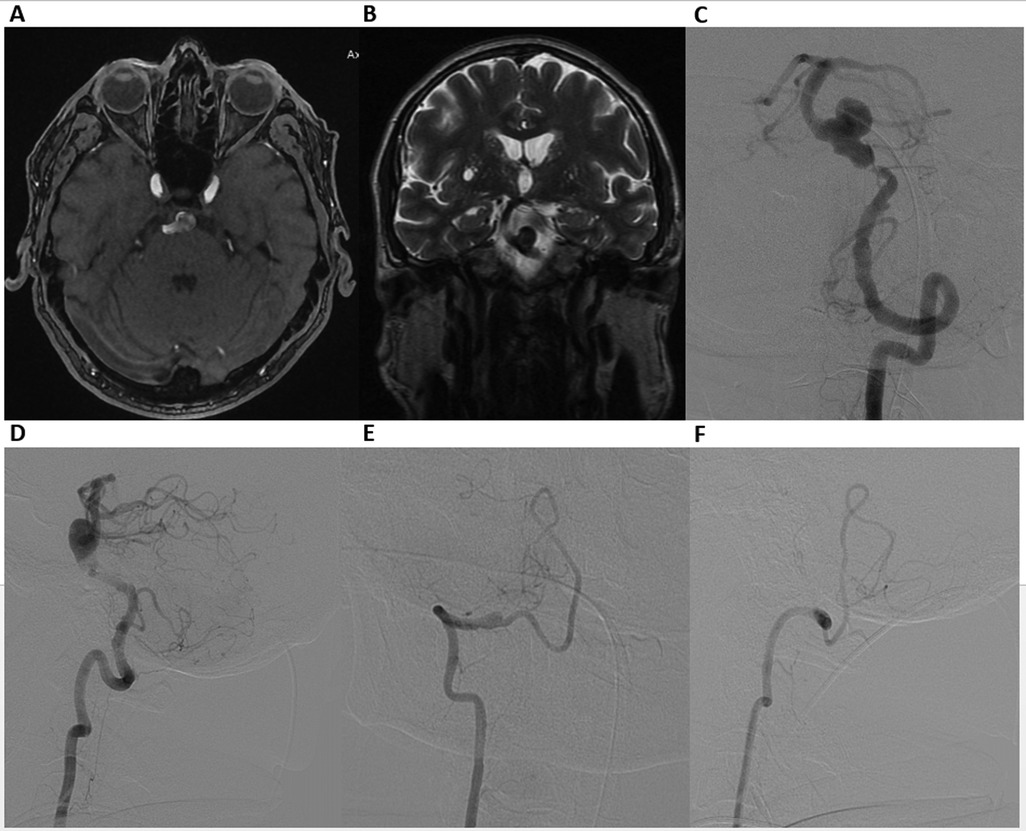

MRI and MR angiography revealed a partially thrombosed BAA (Figures 1A,B). Digital Subtraction Angiography (DSA) confirmed the aneurysm (13 mm × 11 mm) with a wide neck (12 mm) in the inferior third of the BA, accompanied by approximately 90% pre-aneurysmal stenosis (0.5 mm at the level of stenosis), posing a high risk for hemodynamic compromise and potential thromboembolic events (Figures 1C,D). DSA also revealed V4 segment occlusion distal to the right posterior inferior cerebellar artery (Figures 1E,F).

Figure 1. Axial time-of-flight (TOF) MR angiography (A), coronal T2-weighted MRI (B), demonstrating a basilar artery aneurysm. Digital Subtraction Angiography. Frontal (C) and lateral (D) views of the left vertebral artery, showing a wide-neck aneurysm in the inferior third of the basilar artery, accompanied by nearly 90% preaneurysmal stenosis. Frontal (E) and lateral (F) views of the right vertebral artery, revealing V4 segment occlusion distal to the right posterior inferior cerebellar artery.